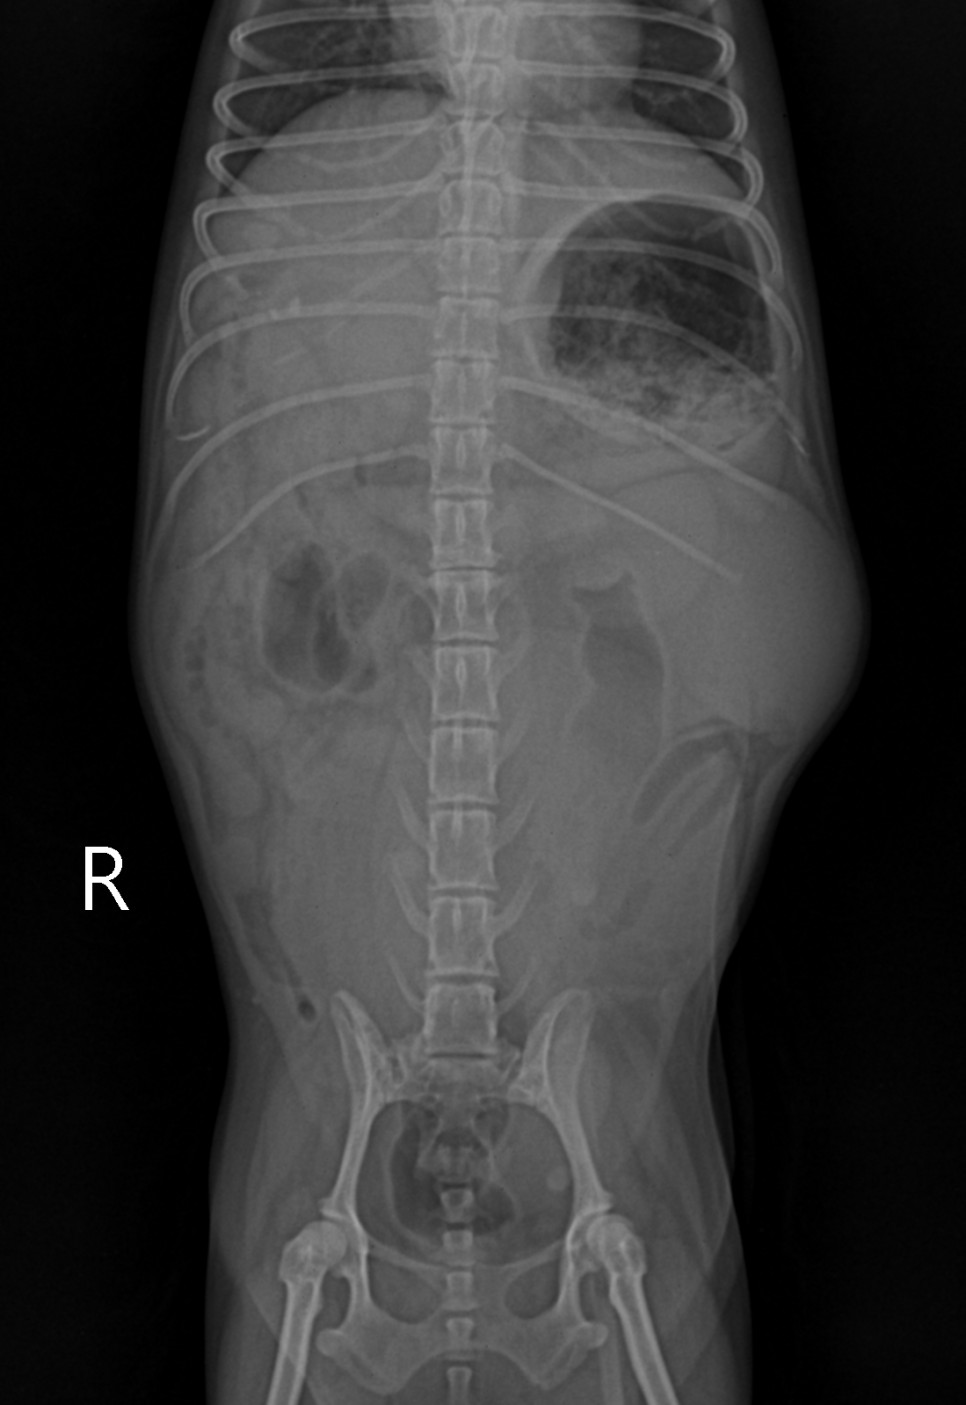

동물 병원에 내원해 주시고, 수의사의 판단으로 검사를 통해 확인이 됩니다.기본적으로 필요한 최소한의 검사는 복부 초음파 검사나 X 선 검사, 혈액 검사 등이 진단에 필요합니다.

신체 검사 결과 생식기 쪽에서 삼출물이 확인되었습니다.자궁 축농이 의심되는 상황이어서 초음파 검사를 통해 확진을 할 수 있었습니다.

초음파 검사를 통해 확장되어 있던 양쪽 자궁을 확인할 수 있었습니다